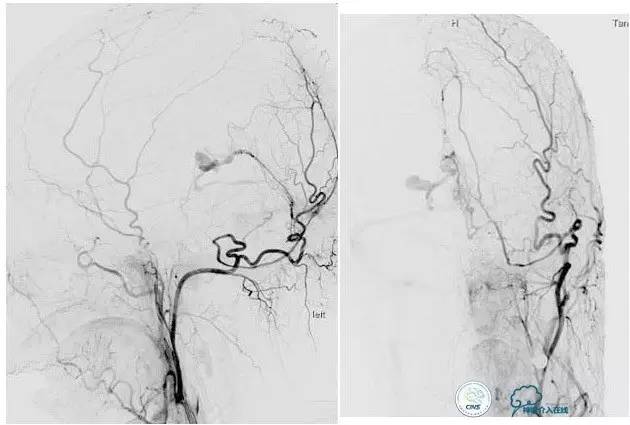

脑膜后动脉供血的小脑幕的瘘。

颈内不参与供血。

大脑后动脉有细小分支供血。

Sceptor球囊无法到达瘘口位置,放在主干内,充盈球囊后把动脉血管床内血液冲洗干净,形成楔入效果。

术后造影【Post embolization】